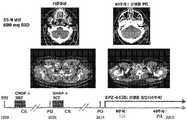

도 9는 원발성 종격동 B 세포 림프종에 있어서 CR(완전 관해)을 나타낸다.

Figure 9 shows CR (complete remission) in primary mediastinal B-cell lymphoma.